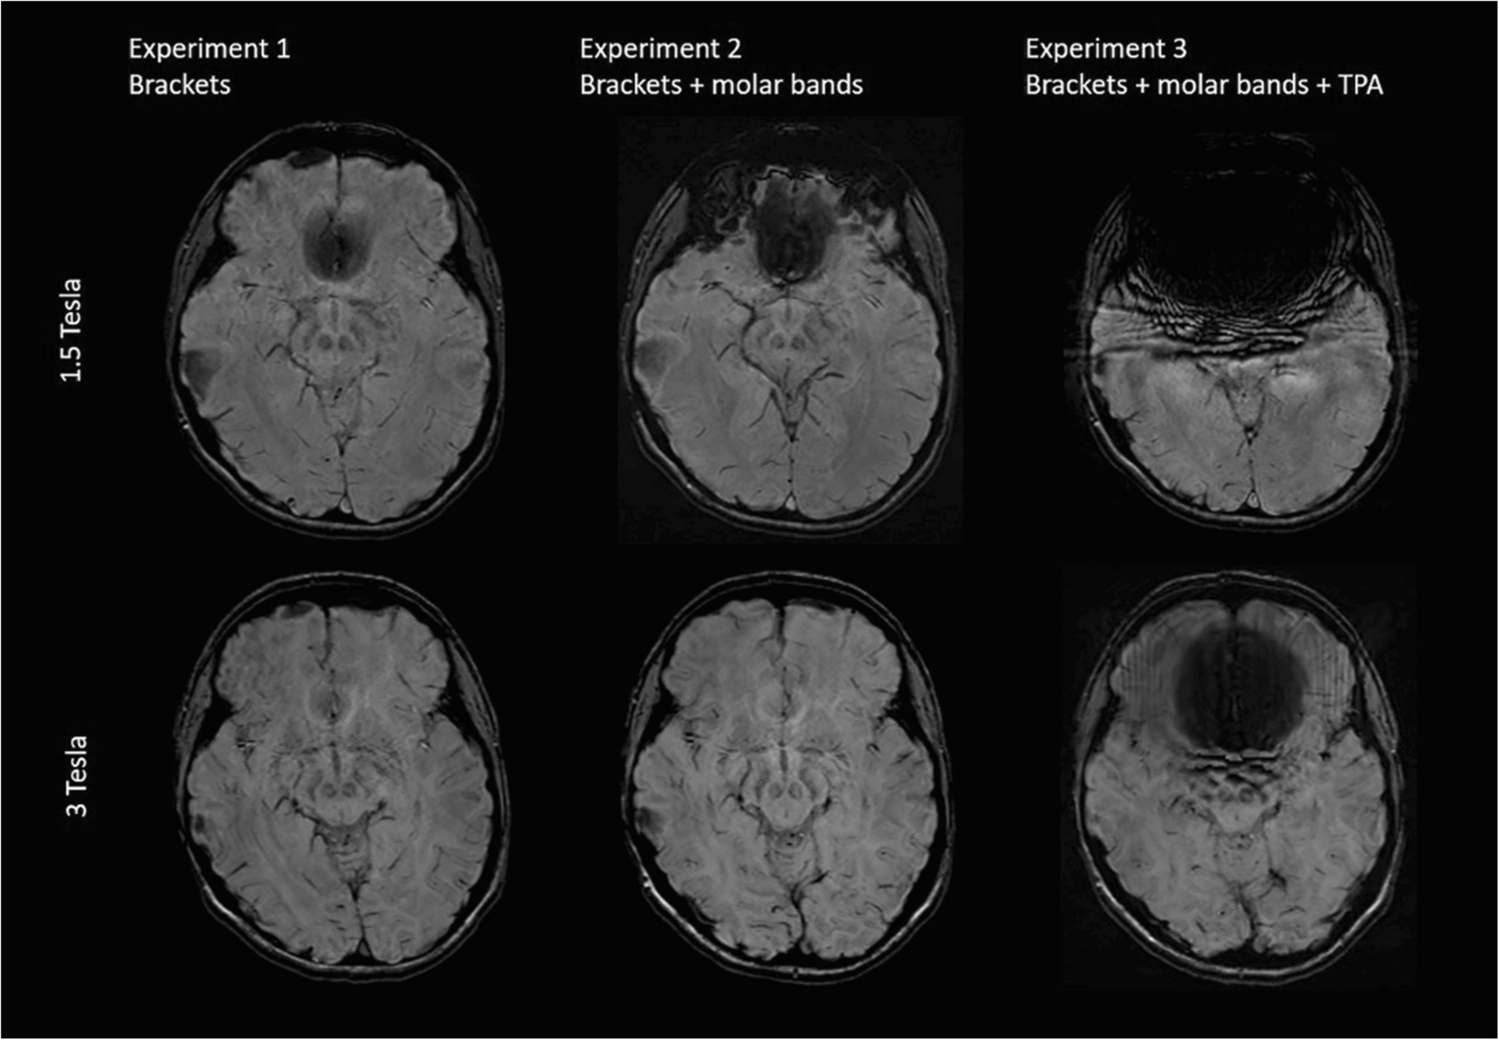

The strongest artifacts are observed in SWI as shown in Figs. 2 and 3, respectively.

Fig. 2

Comparison of representative slices of an axial SWI image from all three volunteer Experiments acquired at 1.5T and 3T

Bild vergrößern

Fig. 3

Comparison of representative slices of a reconstructed sagittal SWI image from all three volunteer Experiments acquired at 1.5T and 3T